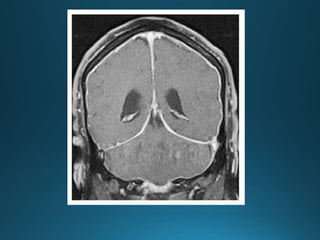

hydrocephalus

État criblé, also known as status cribrosum, is a term that describes the diffusely widened

perivascular spaces (Virchow-Robin spaces) in the basal ganglia, especially in the corpus

striatum. It is usually symmetrical, with the perivascular spaces showing CSF signal and

without diffusion restriction

État criblé, alsoknown as status cribrosum, is a term that describes the diffusely widened perivascular spaces (Virchow-Robin spaces) in the basal ganglia, especially in the corpus striatum. It is usually symmetrical, with the perivascular spaces showing CSF signal and without diffusion restriction